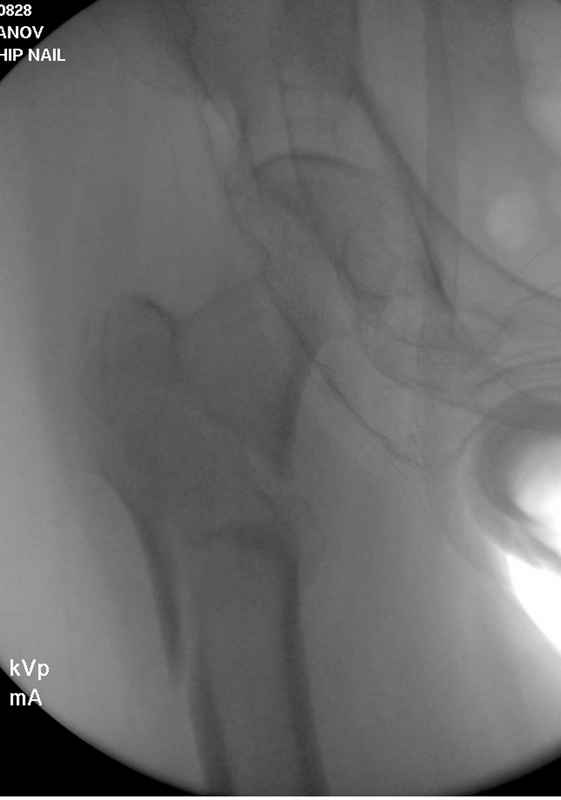

Здесь пара случаев фиксации похожих переломов:

первый высокоэнергетическая травма 36 лет

судя по картинкам с ЭОПа явно использовались приемы непрямой репозиции под его контролем, а так же интраоперационный ЭОП-контроль положения винтов, без такого контроля операция может ухудшить ситуацию (опять же учтите сроки) т.к. результат буде зависеть в большей степени от искусства хирурга, а не от технологии